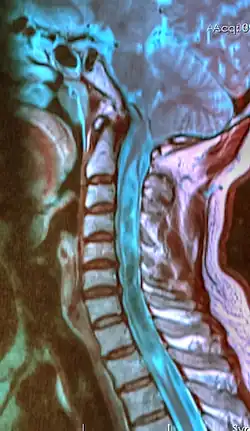

| A sagittal FLAIR MRI scan, from a patient with an Arnold–Chiari malformation, demonstrating tonsillar herniation of 7 mm. | |